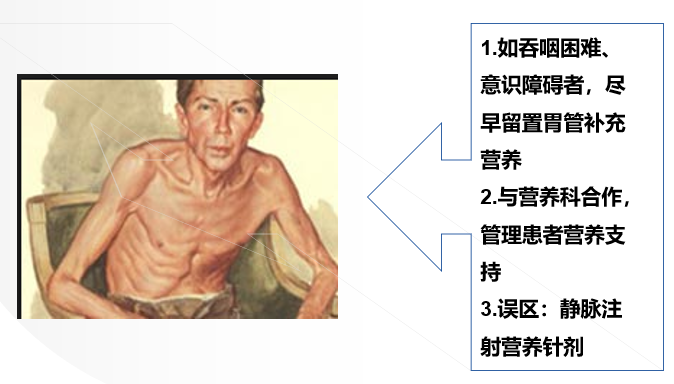

⑤营养障碍